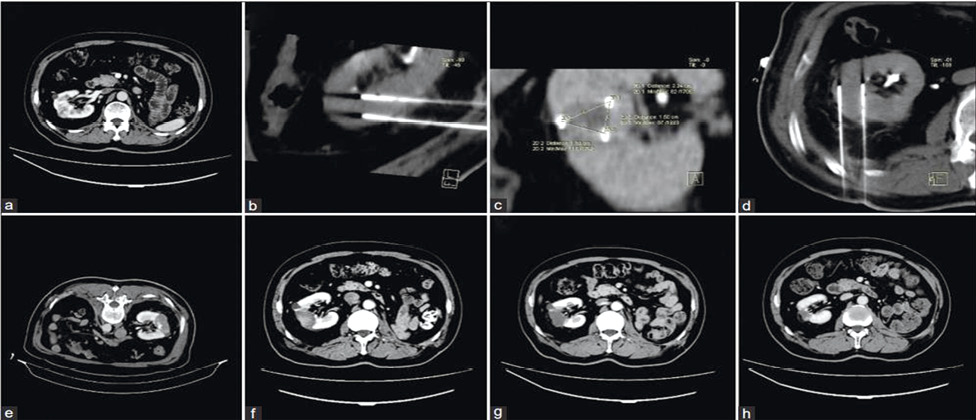

Візуалізаційний контроль проводився в стандартні терміни за допомогою КТ / МРТ із внутрішньовенним підсиленням (рис. 5).

Рис. 5. На передопераційному КТ-зображенні виявлено пухлину в середньому сегменті правої нирки (а). Електроди були введені ззаду, а для точного позиціонування голок електродів використано зображення 3D-реконструкції (b–d). Повторні КТ-зображення одразу після НОЕ та через 1, 3, 12 міс не виявили жодного підсилення в ділянці абляції (e–h) [цит. за 5]